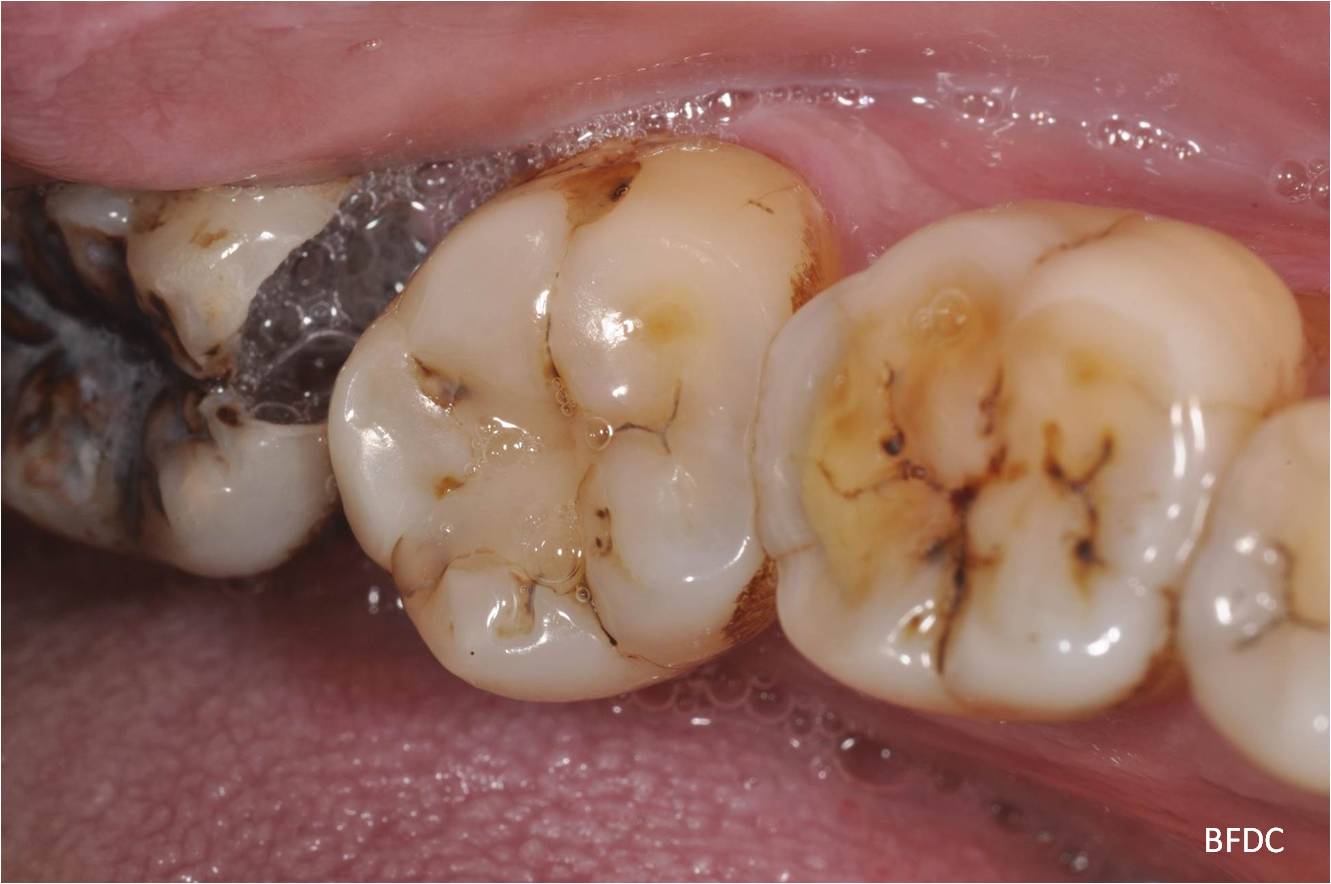

治療前,因智齒蛀牙,容易卡食物

蛀牙已至牙髓,建議先拔除智齒